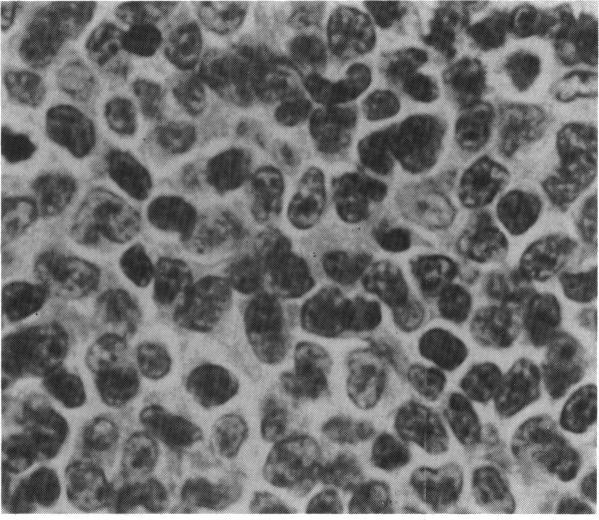

Malignant lymphocytic lymphoma rarely involves the eye. In two patients we found ocular signs and symptoms as the initial presentation of systemic disease. In the first patient periorbital swelling and ptosis of one year's duration ultimately proved to be the result of malignant lymphoma. After resolution of swelling and ptosis with chemotherapy, the patient returned with diffuse iris involvement and uveitis with a hypopyon. In the second patient an acute change of refractive error proved to be the result of a lymphomatous deposit in the choroid. In both instances common symptoms were the initial manifestations of a diffuse malignant disease.